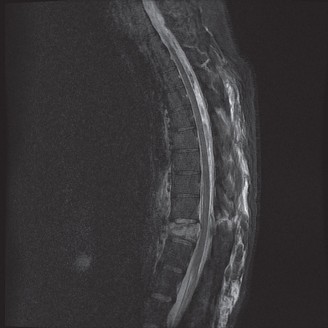

The diagnostic imaging workup for this patient spanned his initial presentation at age 15 and his subsequent return at age 20, providing a textbook illustration of the natural history of untreated isthmic spondylolysis. During his initial visit, standard weight-bearing anteroposterior (AP), lateral, and bilateral oblique radiographs of the lumbar spine were obtained. The lateral radiograph demonstrated a normal lumbar lordosis and preserved L5-S1 disc space height, with no evidence of anterior translation (spondylolisthesis). However, the oblique radiographs revealed the pathognomonic "collar on the Scotty dog" sign. The "Scotty dog" represents the posterior elements of the vertebra, where the nose is the transverse process, the eye is the pedicle, the front leg is the inferior articular process, and the neck is the pars interarticularis. A radiolucent line across the neck confirmed the presence of bilateral L5 pars defects.

Upon his return five years later, the imaging profile was drastically different. Standing lateral radiographs now revealed a Meyerding Grade 2 spondylolisthesis at L5-S1, indicating that the L5 vertebral body had translated anteriorly by 25% to 50% over the sacral promontory. Furthermore, there was a noticeable collapse of the L5-S1 intervertebral disc space, signifying advanced degenerative changes secondary to the altered biomechanics and chronic instability. We also meticulously measured the patient's spinopelvic parameters on a standing 36-inch scoliosis cassette. His Pelvic Incidence (PI) was measured at 65 degrees (high), which mathematically dictates a higher Sacral Slope (SS) and Pelvic Tilt (PT). A high PI is a known biomechanical risk factor for the progression of spondylolisthesis, as it creates a steeper lumbosacral shear angle, placing immense anterior translational force across the compromised L5-S1 segment.

Clinical & Radiographic Imaging Archive